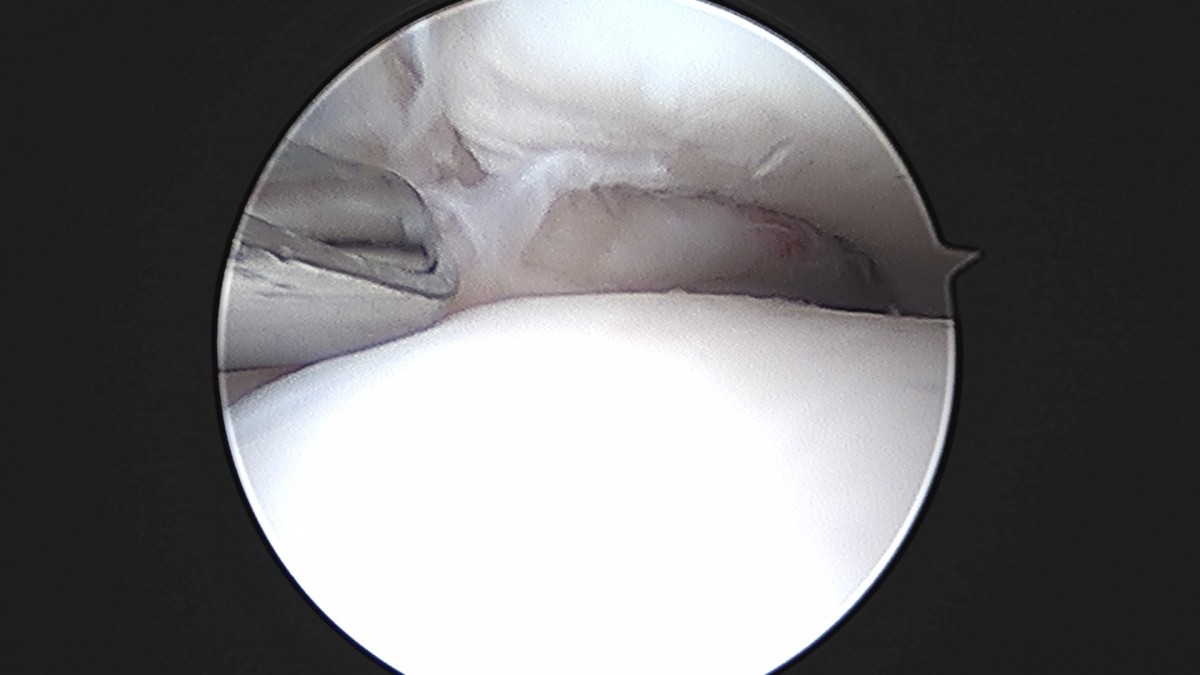

이재상원장님 발목 인대 봉합술 이지O 환자

작성자 최고관리자 댓글 0건 조회 681회 작성일 25-09-16 16:26